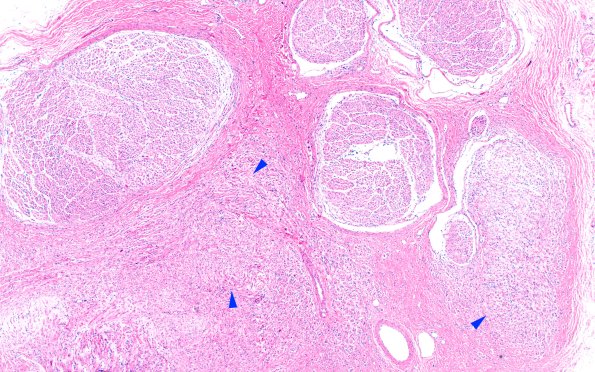

Washington University Experience | PERIPHERAL NEUROPATHY | 19 TRAUMATIC INJURIES | 6A1 Neuroma (Case 6) PROX H&E 4X 1 copy

Sections of the proximal ulnar nerve show multiple fascicles with numerous small groups of axons (mini-fascicles, arrowheads) as expected in a neuroma but many fascicles are not involved at this level. (H&E)